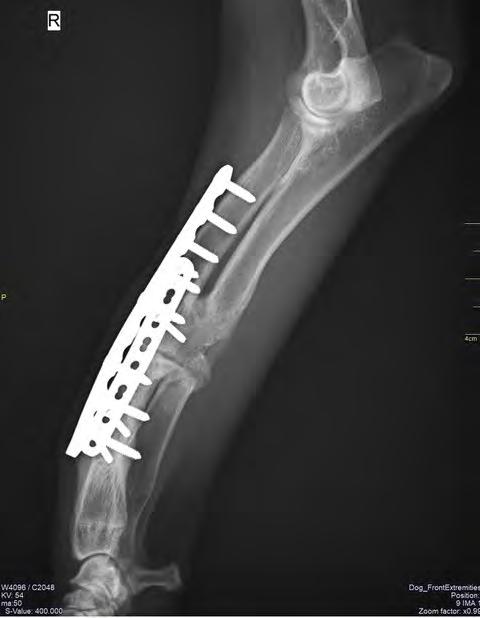

Después de la cirugía se analizaron las radiografías postoperatorias, realizándose las mismas mediciones que en la planificación, y observándose cómo los valores obtenidos tras la cirugía se correspondían con los valores planificados (Fig. 5). Se colocó un vendaje postoperatorio sencillo durante 14 días, para evitar la manipulación del área quirúrgica por parte de la pa-

En cuanto a la evolución, resulta vital realizar radiografías de seguimiento postoperatorio con cierta periodicidad (Fig. 7). Esto nos permite tener un control adecuado del animal y actuar lo antes posible si se presentase algún contratiempo. En el caso que nos

ocupa, además de las radiografías postoperatorias realizadas tras la cirugía correctiva y las efectuadas antes de retirar los implantes, se realizó una TC de revisión tras la extracción de los mismos (al año y dos meses de su colocación), observándose en 3D una buena remodelación y alineación de los huesos. Si comparamos estas imágenes de TC con las primeras, es decir, con las de la planificación quirúrgica antes de la corrección, se puede observar que la superposición de ambas TC muestra una alta precisión en lo que respecta al resultado obtenido (Fig. 8).

Figura 7. Proyecciones radiográficas (A) craneocaudal y (B) mediolateral a los 4 meses de la cirugía. Las imágenes muestran la avanzada consolidación de la ostectomía.